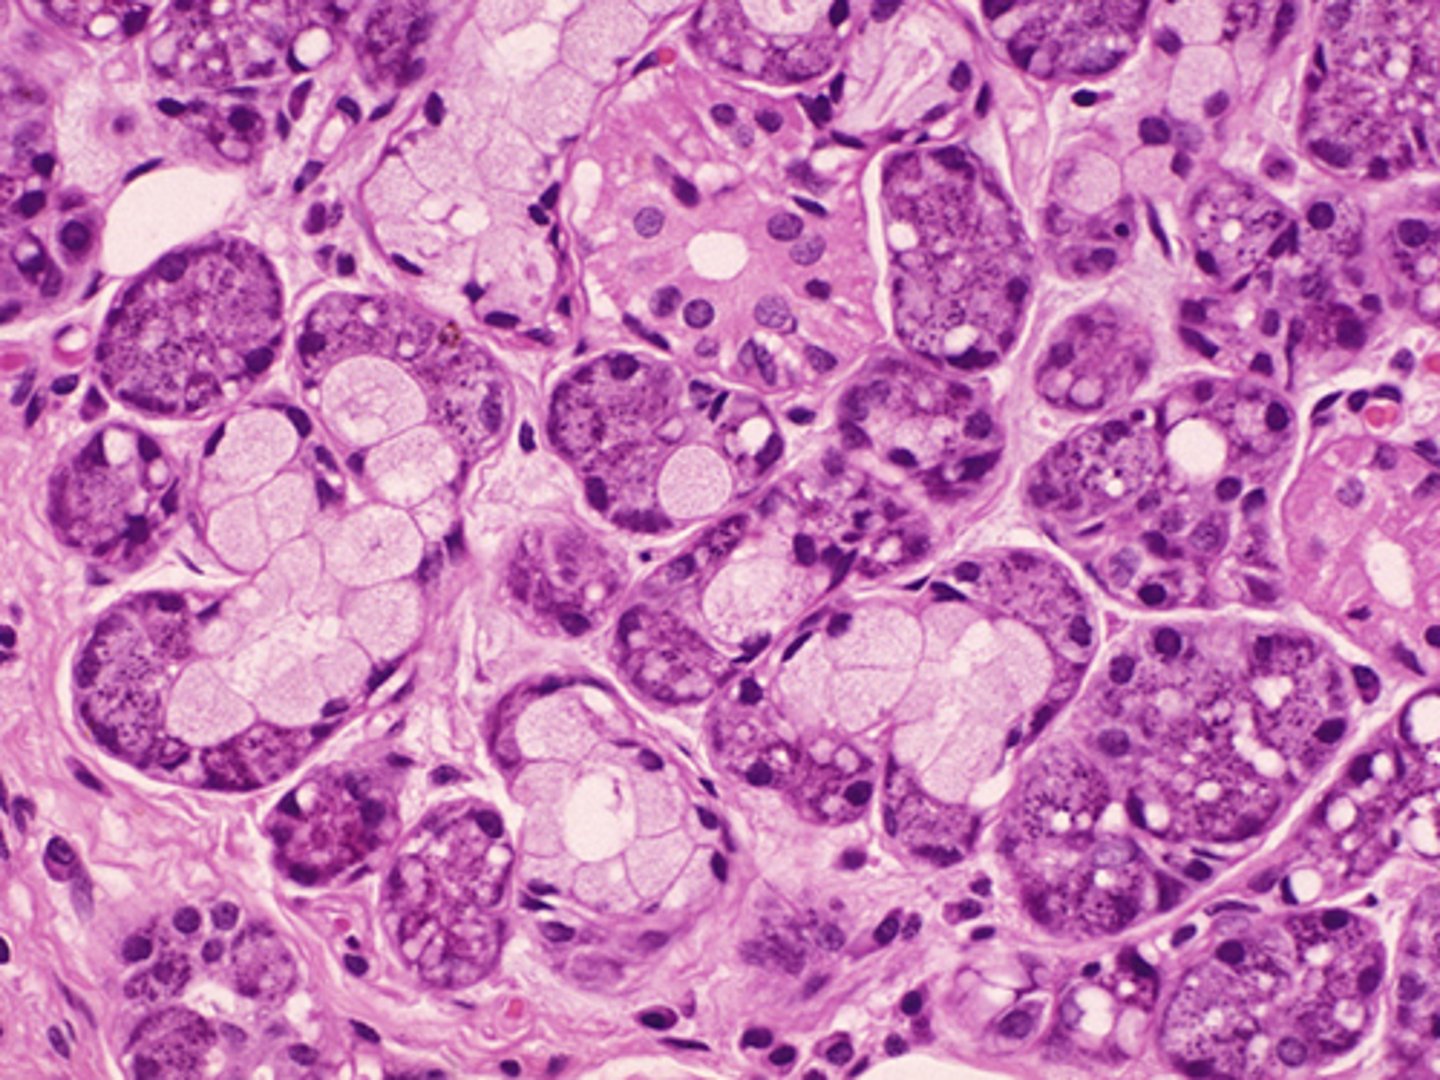

Pancreas

Acinar cells

What cells make up the exocrine portion of the pancreas?

Dump digestive enzymes in the small intestine

What is the function of the pancreas?